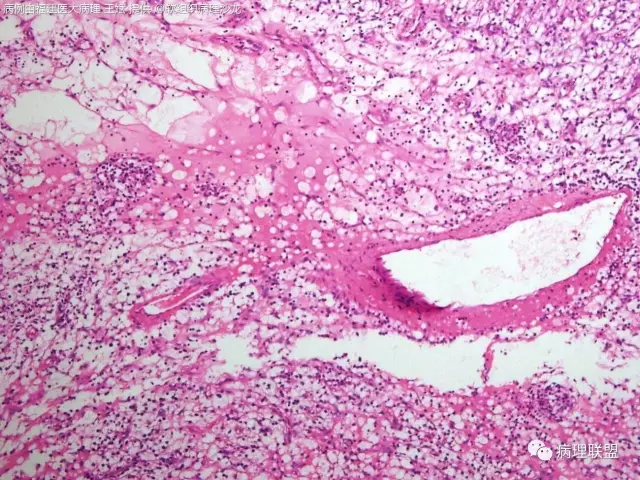

38岁,女性,手部小指背侧皮下肿物,3×2cm(病例由福建医大病理 王斌提供,致谢!)

是的,可以部分有粘液变,我见过的

血管瘤样纤维组织细胞瘤的肿瘤周围有淋巴细胞鞘,结节状分布,有假包膜,出血囊性变的为其主要特点,当然少数病例可以没有出血囊性变却出现粘液变。肿瘤细胞有一定异形性,属于低度恶性或交界性,最好做个FISH,看看有没有EWSR1-CREB1融合基因,刚查了一下,血管瘤样纤维组织细胞瘤还有另一种EWSR1-ATF1融合基因,无论是哪种,用EWSR1分离探针就可以检测